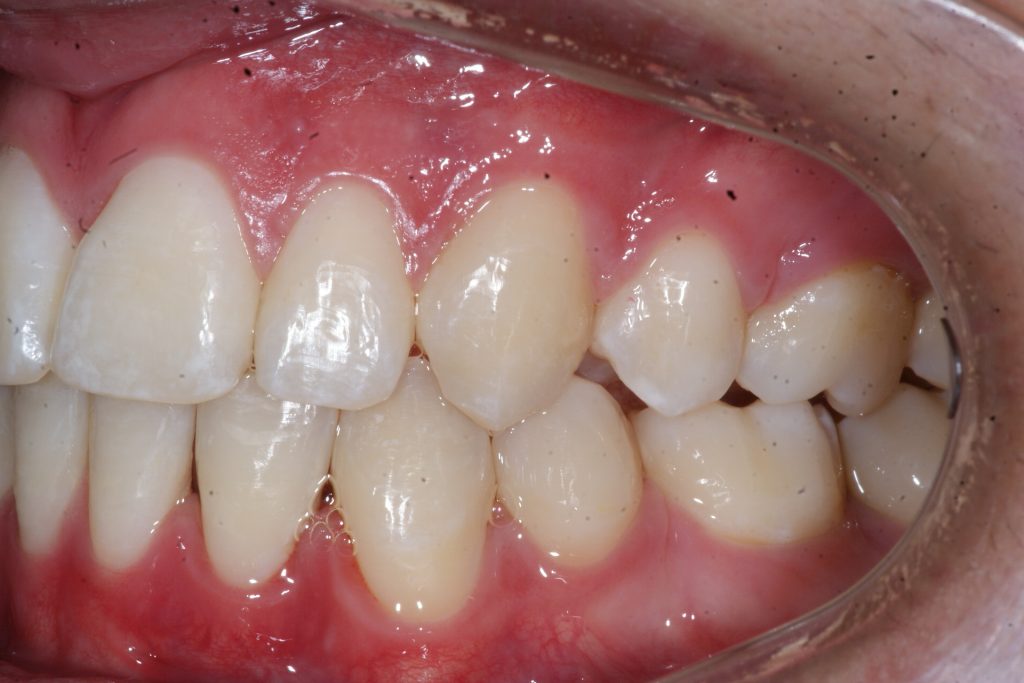

Correction d’une malocclusion de type bimax, canine #33 ectopique et chevauchement léger aux 2 arcades.  Des appareils fixes (broches) et extraction de 4 prémolaires furent nécessaires pour améliorer ce sourire.  Traitement chez un jeune adulte, réalisé en 28 mois.